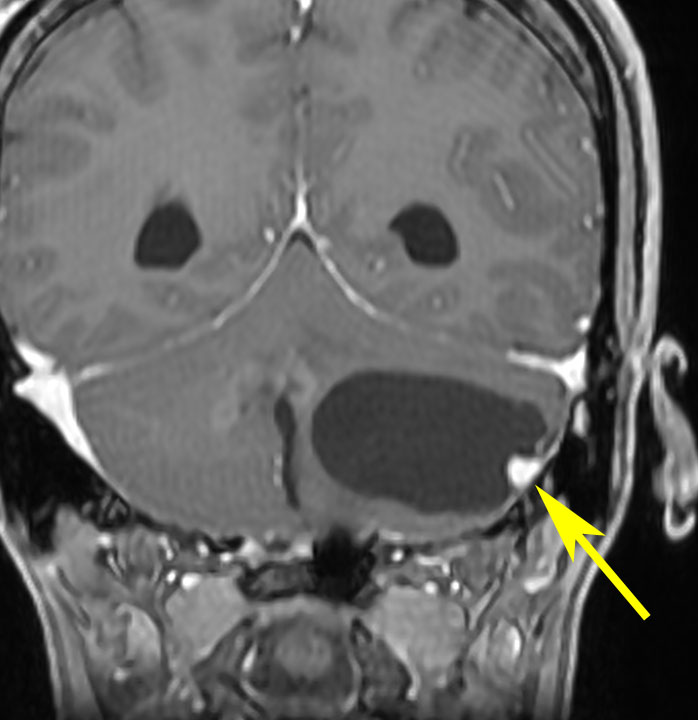

簡単な手術となる例

左右の写真は異なった患者さんのものです。両者ともに,大きな嚢胞(水たまり)を伴う小脳内部の小さな血管芽腫です。右の方に小さく白い塊(黄色の矢印)が見えるのですが,それだけが腫瘍で,濃い灰色に見える部分はのう胞といって液体がたまっているだけです。

これはとても(といっては何ですが比較的に)簡単な手術例です。小脳失調によるふらつきや水頭症よる頭痛と嘔吐などを出しますが,手術後に症状は改善します。

一般に小脳半球という場所にできたものは大きくても手術の成功率はとても高いです。小さいものでは場所と症状によってはガンマナイフなどの放射線治療も有効なことがあります。しかし,手術で摘出できるものは摘出した方が確実に治ります。